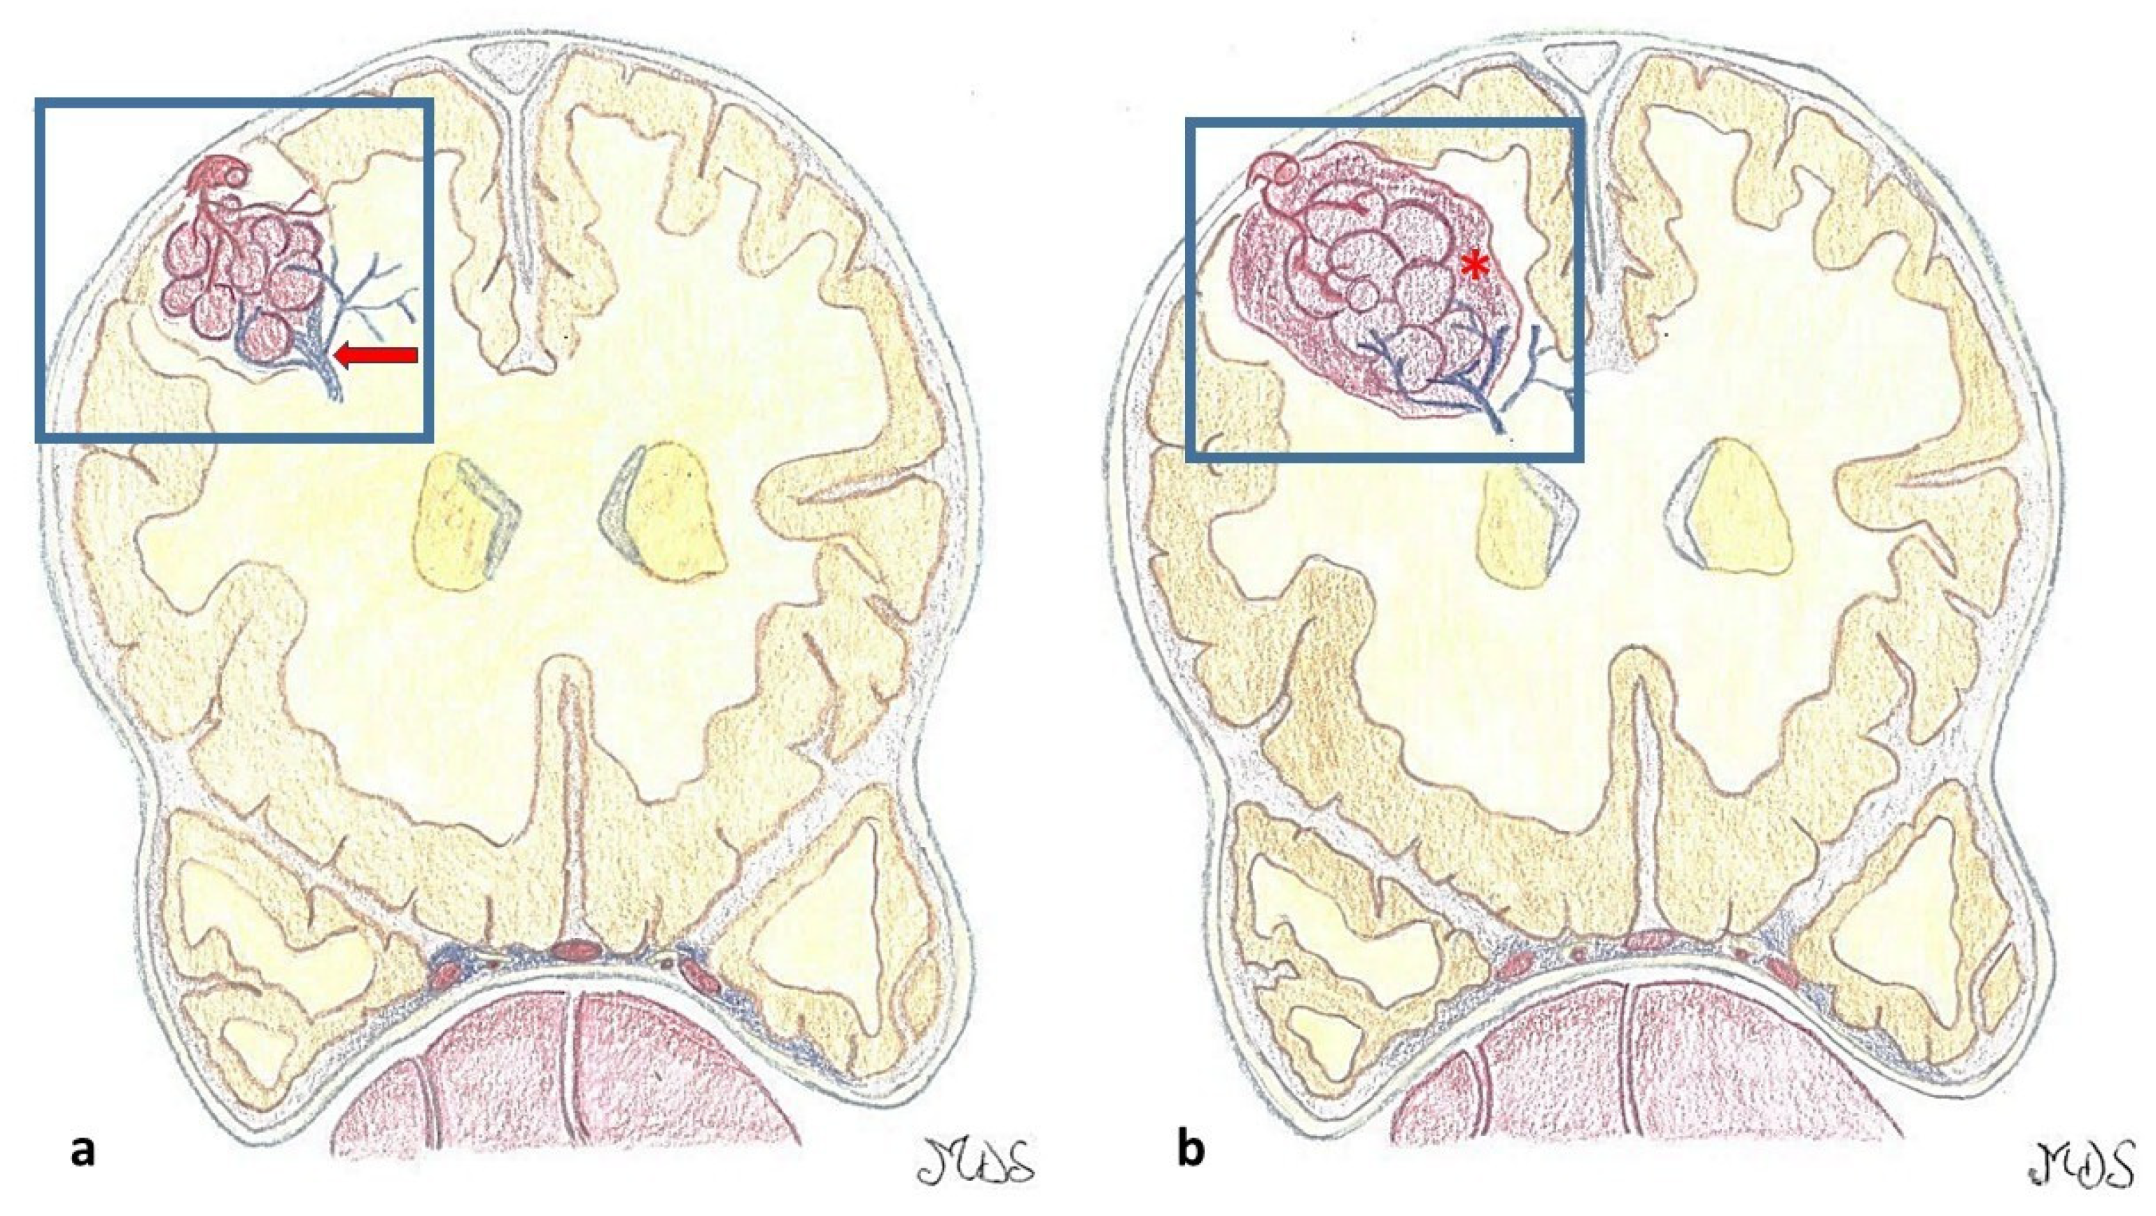

| Lesion Type | MRI Signal | Pathologic Features | Images |

|---|---|---|---|

| Type I | T1: hyperintense core T2: hyper- or hypointense core with surrounding hypointense rim | Subacute hemorrhage surrounded by a rim of hemosiderin-stained macrophages and gliotic brain | ![]() |

| Type II | T1: reticulated mixed signal core T2: reticulated mixed signal core with surrounding hypointense rim resulting in the “popcorn” appearance GE: low signal rim with blooming | Loculated area of hemorrhage and thrombosis of varying age, surrounded by gliotic, hemosiderin-stained brain; in large lesions, areas of calcification may be seen | ![]() |

| Type III | T1: iso- or hypointense T2: hypointense with a hypointense rim that magnifies the size of the lesion GE: hypointense with greater magnification than T2 | Chronic resolved hemorrhage, with hemosiderin staining within and around the lesion | ![]() |

| Type IV | T1: poorly seen or not visualized at all T2: poorly seen or not visualized at all GE: punctate hypointense lesions | Thought to be capillary telangiectasias | ![]() |